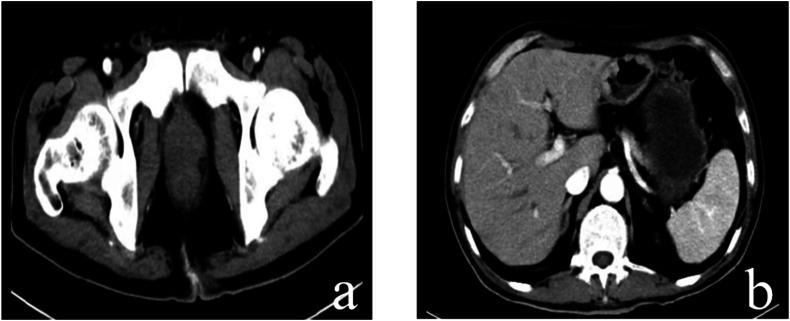

Tislelizumab: An effective anti-PD-1 antibody for the treatment of advanced basal cell carcinoma of the prostate.

Basal cell carcinoma (BCC) of the prostate is a rare and enigmatic tumor with uncertain biological behavior and treatment modalities. Some studies suggest that BCC exhibits invasive characteristics and a high degree of malignancy, necessitating proactive management and vigilant monitoring. Notably, there is a lack of reported effective treatment utilizing programmed cell death protein-1 (PD-1) inhibitors for advanced BCC of the prostate. This study explores the efficacy of tislelizumab, as a single-agent therapy, in the successful treatment of advanced prostate BCC.